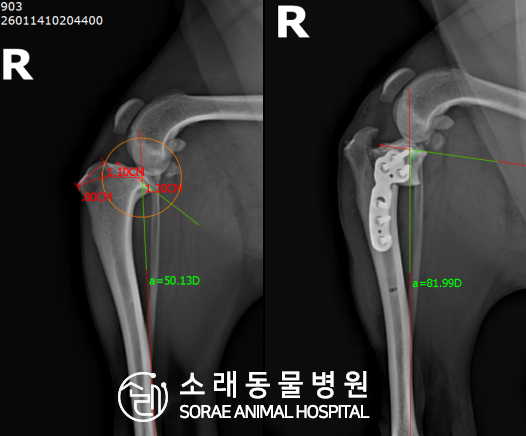

계산식으로 사전에 계획해두었던 플랜에 따라 경골을 절제하고

플레이트와 스크류를 사용하여 임플란트를 적용해 주었습니다.

반대 방향으로 밀려나 어긋나있던 대퇴골과 정강이가

제 자리를 찾으면서 무릎의 각도가 교정된 것을 확인할 수 있습니다